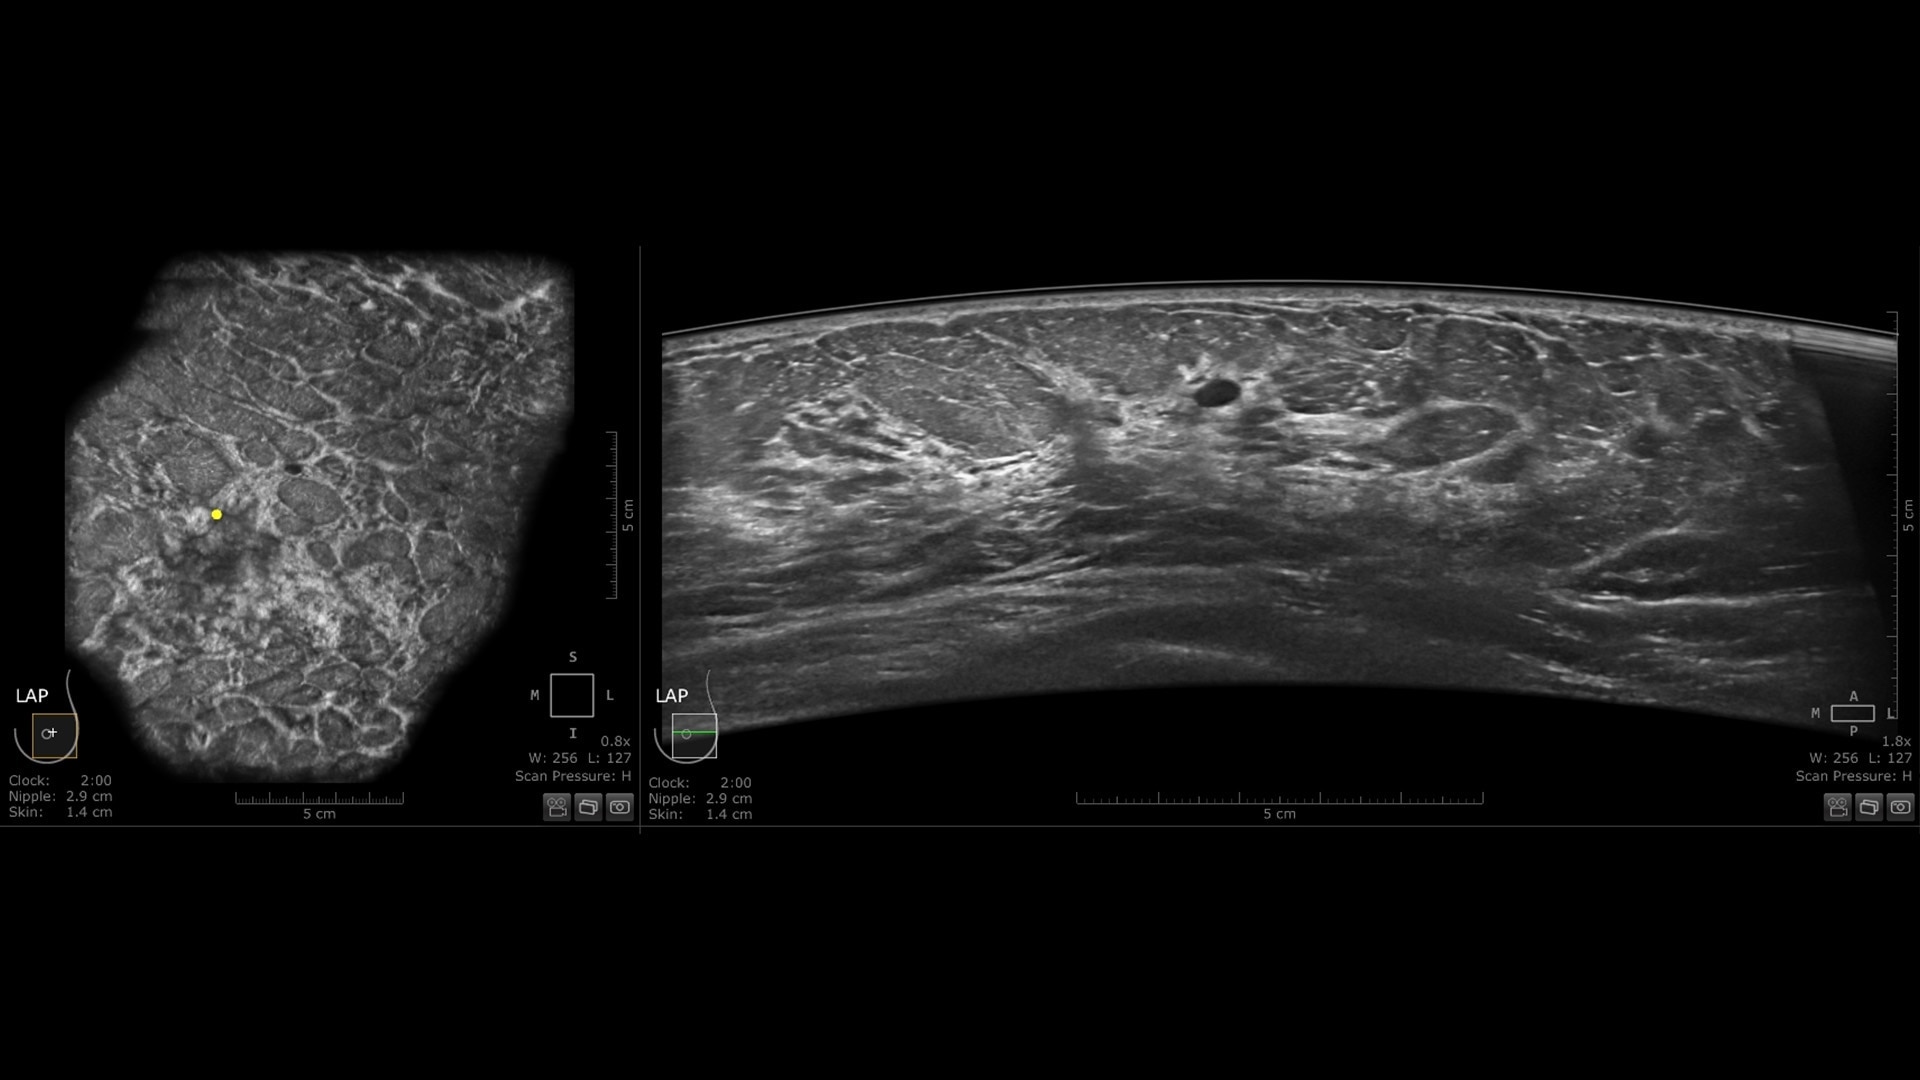

Productivity powered by AI

Boost clinical confidence and efficiency with AI-driven scanning and reading